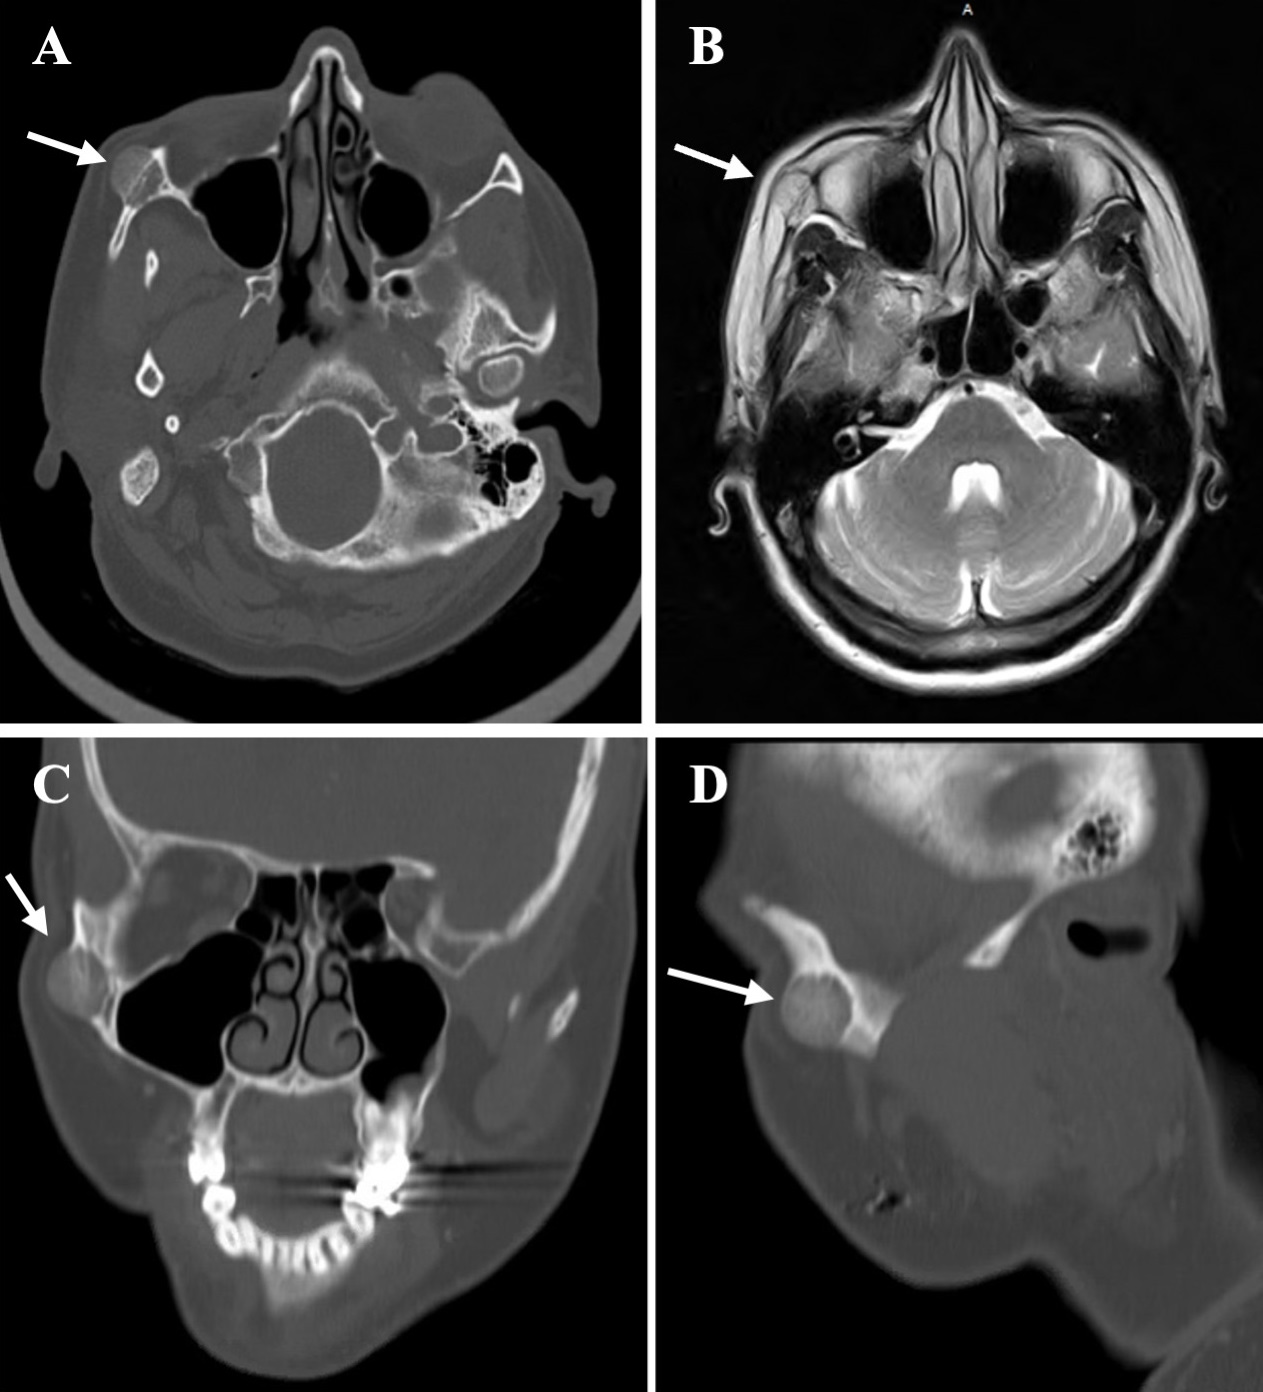

Magnetic resonance imaging with contrast of the face and orbit revealed a 1.5 × 1.3 × 1.6-cm T1 hypointense and T2 hyperintense enhancing mass, suggestive of a hyper-vascular lesion at the lateral right orbital rim – anterior zygomatic arch junction (Figure 1). Subsequently, an osseous skeletal survey was completed to rule out plasmacytoma.

Figure 1. Imaging showing mass along the junction of the lateral right orbit and anterior zygomatic arch and magnetic resonance imaging showing an incidental pituitary macroadenoma: (A) Axial caudal computed tomography scan with mass. (B) Axial T2-weighted magnetic resonance image with hyperintense mass. (C) Coronal and (D) sagittal computed tomography scan with mass.